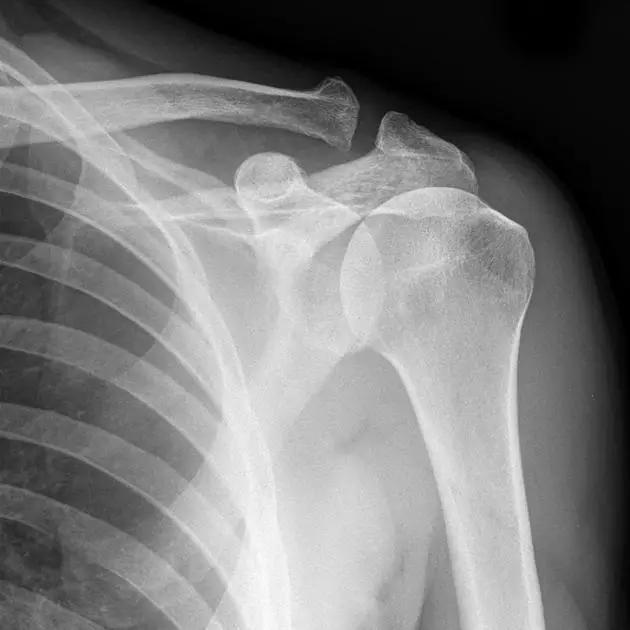

正常肩关节(来源:Radiopaedia)

Hill-Sachs 损伤的 X 片(来源:Hill-Sachs Injuries of the Shoulder)